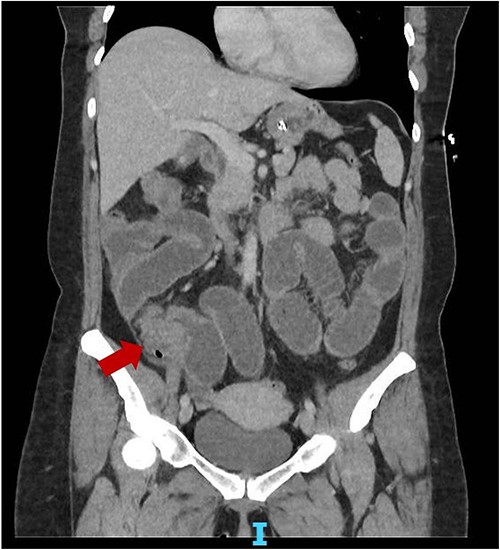

She represented 4 months later with similar symptoms and vomiting. Again, a non-con CT was done showing similar findings to the first CT. On retrospective review of the CT, there might have been a mass present close to the IC valve (Fig. 1). A repeat CT with IV contrast was done within the same admission, which showed a possible stricture at the terminal ileum (TI). Her faecal calprotectin was high at 95.8 μg/g (<50). Blood tests were unremarkable. Again, she resolved with conservative management and was discharged with a plan for an outpatient magnetic resonance enterography (MRE) and colonoscopy.

Coronal slice CT abdomen pelvis showing SBO with transition point at the distal ileum secondary to a possible mass.